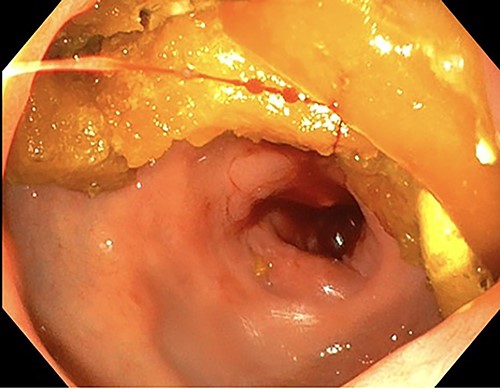

A 76-year-old lady presented to the outpatient clinic with a history of lower abdominal bloating and lethargy for 1 week. The patient denied abdominal pain, nausea, altered bowel habits or GI bleeding. Her past medical history included gastroesophageal reflux disease, ulcerative colitis and a previous hysterectomy. Physical examination exhibited pallor of the conjunctiva, distended abdomen with visible peristalsis on inspection but soft, non-tender on palpation and absence of ascites. Laboratory testing found normocytic normochromic anaemia, thrombocytosis and a positive myeloma screen with elevated kappa to lambda free light chain ratio despite normal renal and liver function. An ultrasound of the abdomen was unremarkable. Computed tomography (CT) with IV contrast of the abdomen revealed diffuse thickening of the small and large bowel with the small bowel dilated throughout. Magnetic resonance imaging of the small bowel showed multiple abnormally thickened loops of the jejunum and proximal ileum with a maximal wall thickness of 0.9 cm (Figs 1 and 2). Gastroscopy revealed severe distal oesophagitis, the stomach contained patchy telangiectasia and gastritis with sloughy mucosa at the incisura in addition to duodenitis with stricture at the second part of duodenum (D2) (Figs 3 and 4). Histopathology from the biopsies of the gastric incisura, D2 and the proximal jejunum displayed reactive changes with intramucosal haemorrhage and extensive deposition of pink amorphous, eosinophilic material on haematoxylin & eosin (H&E) stain. The deposits were predominantly seen in the proximal jejunum with a positive Congo red stain showing apple-green birefringence under polarized light (Figs 5 and 6). The patient was referred to Haematology, and a bone marrow aspirate and trephine biopsy revealed proliferation of 15% mature plasma cells consistent with the diagnosis of myeloma.

Endoscopy showing duodenitis with stricture at the second part of duodenum (D2).